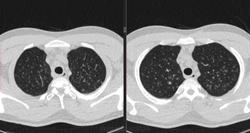

По jpeg впечатление очаговых изменений верхних долей и умеренного увеличения лимфоузлов средостения. Туберкулез на первое место.

Моё мнение то же самое, туберкулез. Добавила изображения.

Посев мокроты на туберкулез отрицательный. Пульмонолог по КТ ставит саркоидоз легких 2 степени. Какое Ваше мнение?

В диф. ряд на первое место предполагаю все же саркоидоз легких и ВГЛУ (по одной из классификаций 2 стадия, а не степень). В плане дальнейшего диагностического алгоритма: